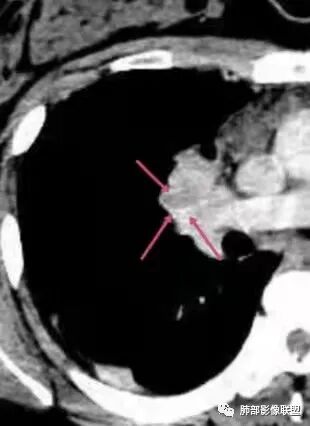

本例患者,年轻女性,慢性病程,多次抗感染治疗效果不佳,实验室检查示白细胞及中性粒细胞不高,不支持普通细菌感染,虽然肺泡灌洗液X-Pert检测阴性,结合患者胸部CT结核感染亦不能排除,胸部CT主要表现为右侧肺门及纵隔淋巴结肿大,仔细观察不难发现右中间支气管内新生物凸向管腔内,增强扫描,右肺门(10R)及纵隔淋巴结(2R,4R)明显不均匀强化,内部呈不规则低密度无强化区,被周边高强化区包绕(环形强化)的特点,首先应当想到纵隔淋巴结结核诊断。淋巴结分布亦不符合肺部恶性肿瘤迁徙途径。